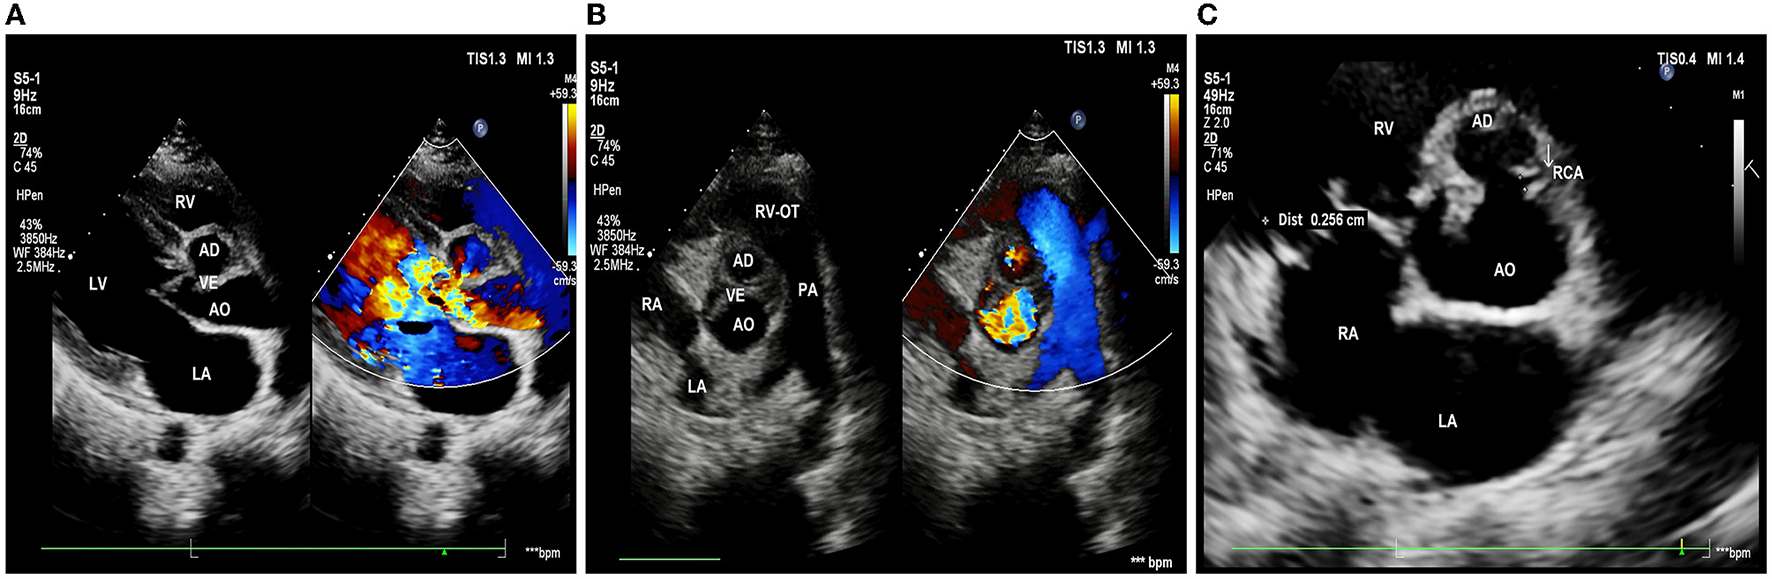

Echocardiography showed: left ventricle enlargement; a sonolucent area ~11.5 × 25 mm was located next to the right coronary sinus, which communicated with the dilated aortic root; a flail-like moving flocculent vegetation ~17 mm long was located in the junction area of the right and left aortic valve on the aortic side; the right and left aortic valve leaflets were both impaired, resulting in severe aortic regurgitation (Figures 1A, B); and the right coronary artery showed intramural course and was compressed by the surrounding abscess. It also showed an abnormal opening at the junction of the left and right aortic valves, with only a 2.7 mm wide ostium compared to a 4.3 mm one in the left coronary artery (Figure 1C); the ejection fraction was 69%; mild pulmonary hypertension was presented; and no obvious abnormality was observed in the aortic arch and its branches.

Figure 1

Pre-operative echocardiography. (A) Long-axis view of the left ventricle shows aortic valves thickening and flail motion, and color Doppler shows massive aortic regurgitation. (B) Short-axis view of the great arteries shows that the bulge in the aortic root communicates with the aorta, with vegetations in the aortic valve. (C) The right coronary artery (white arrow) is restrictive; LA, left atrium; LV, left ventricle; RV, right ventricle; AO, aorta; RVOT, right ventricular outflow tract; PA, pulmonary artery; RCA, right coronary artery; AD, aortic disease; and VE, valvular excrescence.